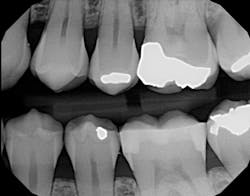

In another case, I used All-Bond Universal to fill a very typical Class II restoration for a female patient (figure 3). By this time, my assistant and I applied the bonding agent with ease and left the instruction sheet behind. Although I did not get to test All-Bond Universal's versatility with other procedures, I look forward to using it for indirect restorations in the future.

Figure 3: All-Bond Universal restoration